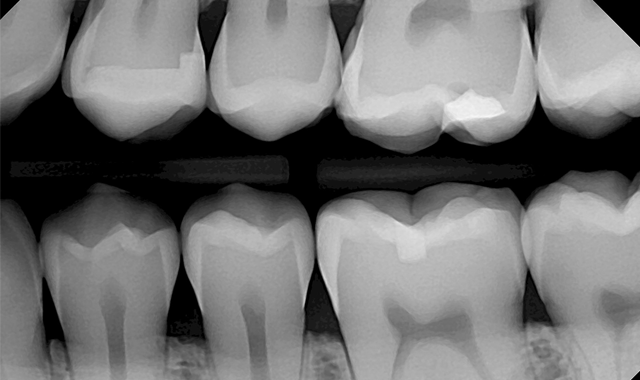

In dentistry, radiographic images play a major role in diagnosis. In order to arrive at an accurate diagnosis, it is critical to have a high quality radiographic image. And what is the best way to achieve high-quality images in this day and age? I believe that most dentists will agree that digital sensors are the answer.

However, it is important to mention that there is more to achieving good images than simply having good technique. If you really want to obtain good quality images, you will also need to use high-quality sensors. After doing some research and trying a few sensors, I found that the DentiMax Dream Sensor delivered excellent image quality.

The images were as good or better than the competitors’ images. Surprisingly, the price was much lower than the other sensors I had sampled. I was very happy to find a sensor that delivered such excellent images at such a reasonable price.

Once you learn how to get the most out of your sensors and become familiar with the software, the results are just phenomenal. With sensors, I am getting higher quality images than with film, which allows me to detect pathology better. If we have to retake an image, sensors save us a lot of time because I can see the image immediately and retake the image within seconds.